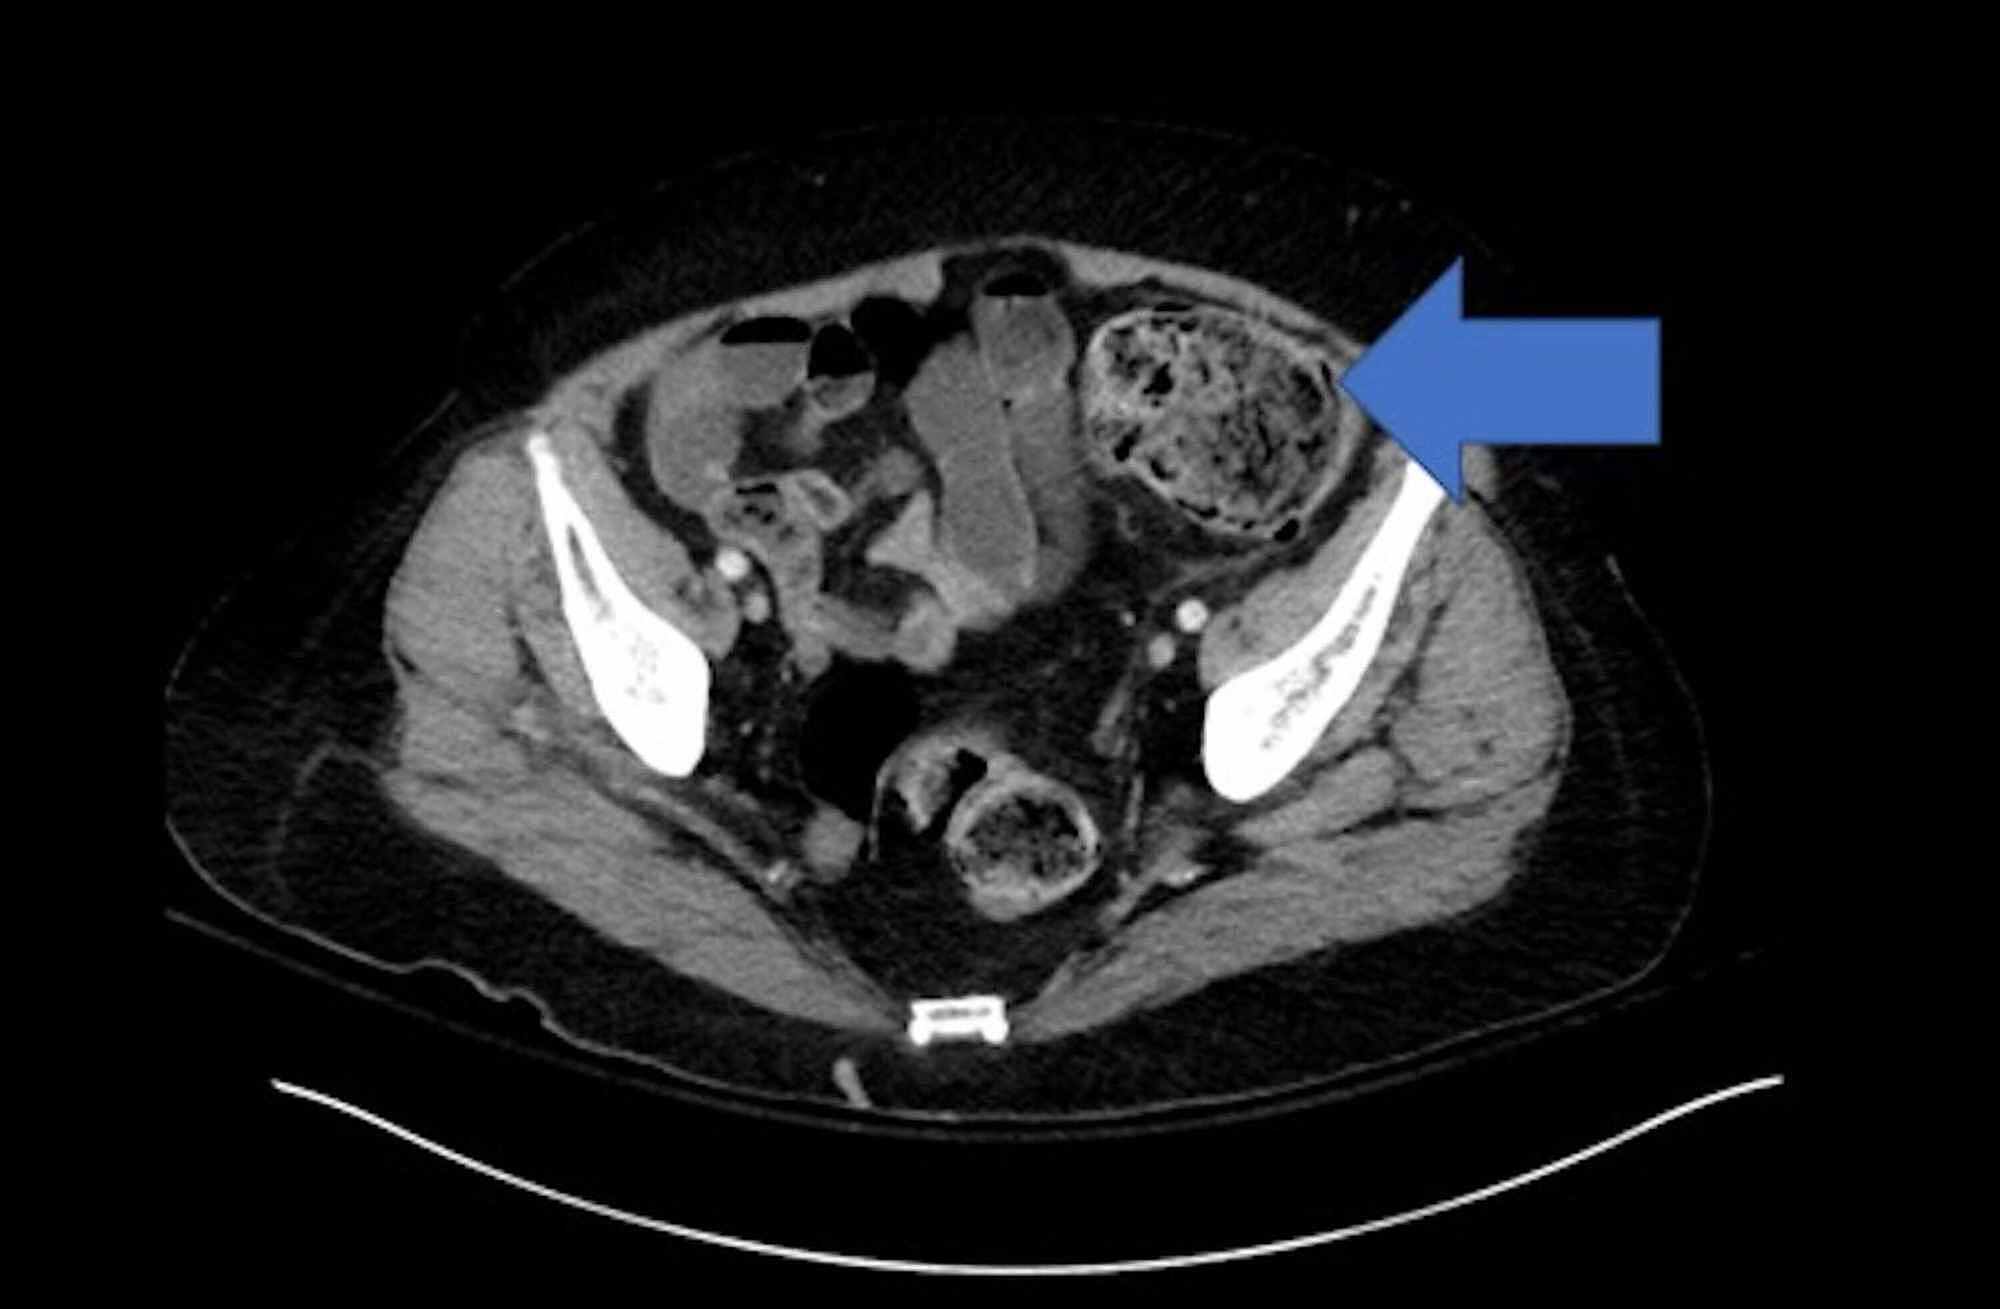

Ischemic Colitis On Ct .   this paper aims at evaluating ct findings of occlusive and nonocclusive.   ischaemic colitis occurs when there is an acute, transient compromise in blood flow, below that required for. To summarize the frequency of findings on iv contrast, enhanced computer tomography (ct) in.   ct in acute abdomen is useful to exclude serious medical conditions.  the most frequently observed ct findings in ischemic colitis in our series were fat stranding, wall thickening, and abnormal.   ct with intravenous contrast is the imaging modality of choice.  manifestations of ischemic colitis on ct include colonic wall thickening, edema, thumbprinting, bowel dilatation, and effusion of intestinal circumference.